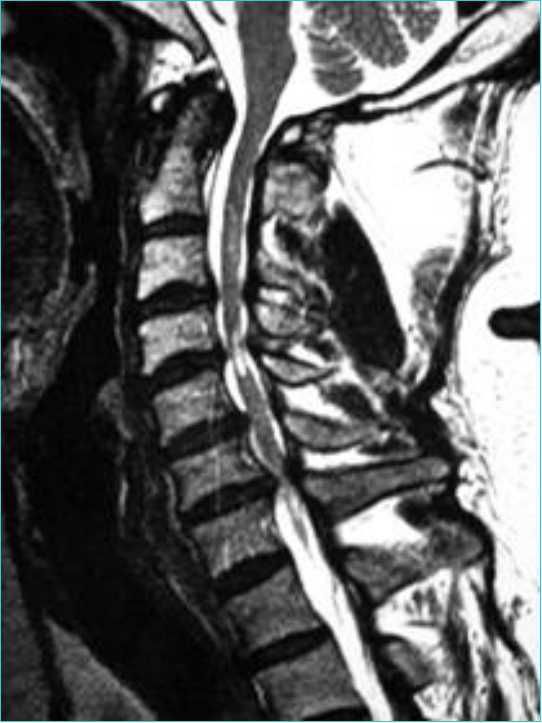

上肢肩背部僵硬麻木疼痛萎缩是什么病--神经根

542x723 - 35KB - JPEG